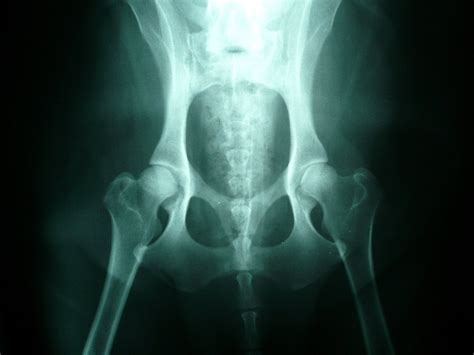

Ochorenie sa dá zdiagnostikovať a určiť stupeň dysplázie jedine RTG vyšetrením vykonanom v celkovej anestézii na oficiálne schválenom RTG pracovisku. Od 12 týždňov veku je možné vykonať tzv. rannú diagnostiku DBK. V prípade podozrenia na dyspláziu sa diagnostika vykonáva ihneď bez ohľadu na vek.

Pri vyšetrení sa sleduje laxicita kĺbov a následne pri rntgenologickom vyšetrení sa meria miera pohyblivosti kĺbovej hlavice ku kĺbovej jamke. Na Slovensku sú momentálne do chovu uznané len psy so stupňom 0 a 1, resp. A 0/0 - B 1/1. Pre účely chovnosti je jedinec vyšetrovaný po dosiahnutí určitého veku (v závislosti od plemena od 12,18, či 24 mesiacov). Po posúdení RTG snímku na chovné účely je vyhodnotený certifikát s výsledkom, ktorý je zároveň zapísaný aj do PP. Na hodnotenie sa u nás (podobne ako vo väčšine európskych krajín) používa 5-stupňový systém, škála hodnotenia je od A - E alebo 0 až 4. Dysplázia bedrového kĺbu sa medzinárodne označuje ako HD (hip dysplasia). Vyhodnocuje sa ľavý i pravý kĺb, zápisy HD 0/0 alebo HD A/A predstavujú zdravé kĺby bez nálezu. Čím vyššie číslo (resp. písmeno), tým vyšší stupeň dysplázie.

Na diagnostiku ochorenia sa používa röntgenové vyšetrenie za pomoci RTG prístroja. Pre komplexné posúdenie stavu bedier je potrebné vyšetrenie vykonať v úplnej anestézii. Anestézia je potrebná z dôvodu uvoľnenia svalov a dosiahnutia najlepšej polohy pre RTG vyšetrenie bedier. Diagnostiku je možné vykonať už od 12 týždňov veku šteniatka. V závislosti od predispozícii a konkrétneho plemena sa vyšetrenie môže opakovať po dosiahnutí 3, 12 alebo 24 mesiacov.

Chov ČsV a DBK: Podmienkou uchovnenia československého vlčiaka je aj vyšetrenie na toto ochorenie. Vyhodnotenie robí len jeden veterinár na Slovensku, aby zostalo objektívne. Vyšetrenie sa robí pomocou RTG, je bezbolestné. Snímky sa zhotovujú z oboch kĺbov, ako u DBK, tak u DLK, jednak pre porovnanie kĺbov a tiež, že je vysoko pravdepodobné, že poškodené sú oba kĺby.